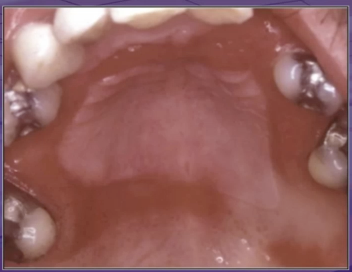

what is the cause of this lesion

wearing denture all the time

trauma

bacterial infection

unknown